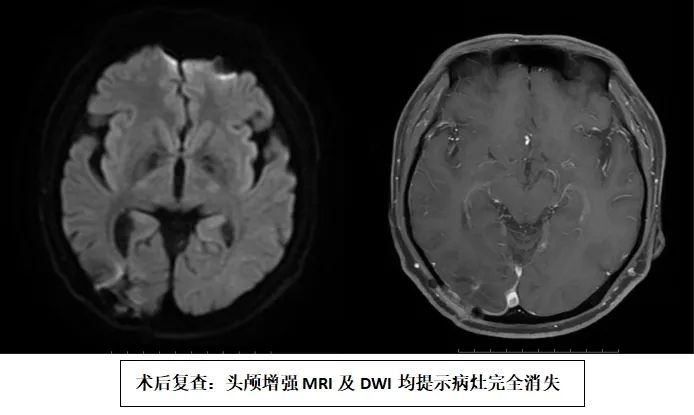

【医讯速览·新闻】第127期:专业铸就信任 实力见证奇迹——我院神经外科成功完成院内首例脑脓肿切除术